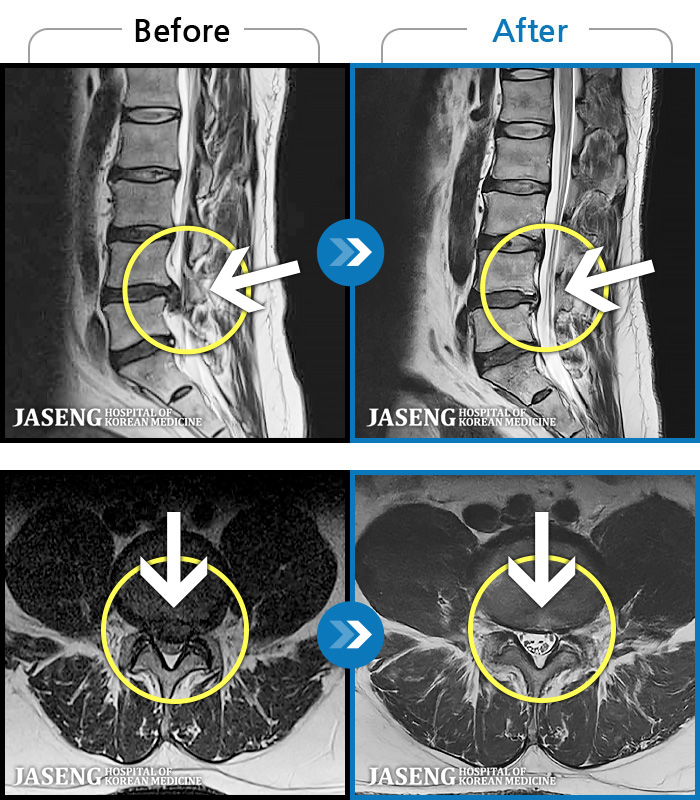

- MRI ġ

MRI ġ

1,237 MRI ũ ʸ Ȯϼ.